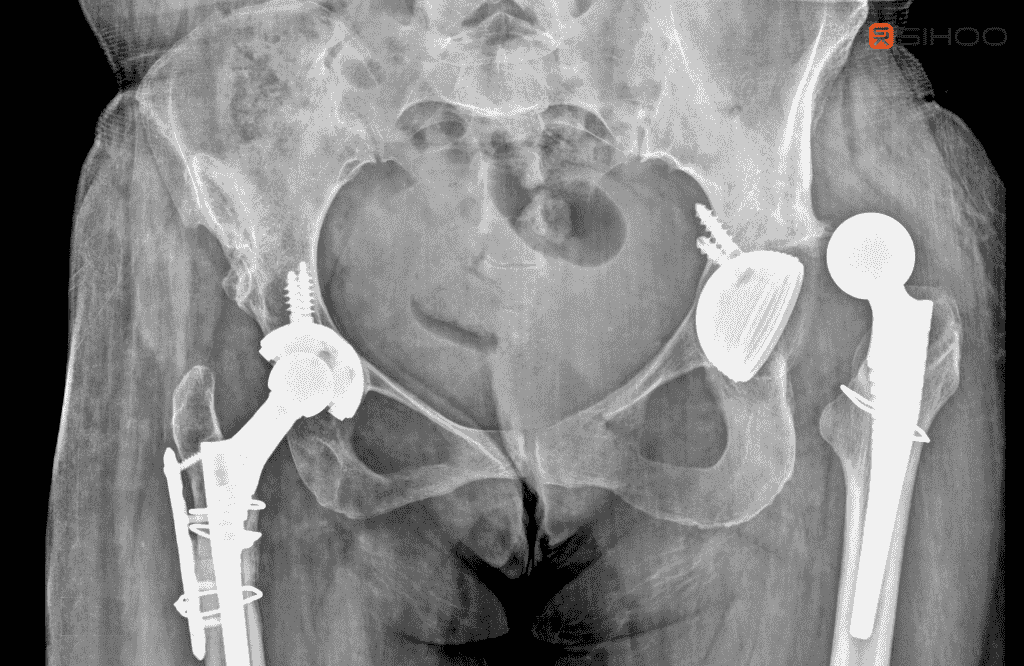

Hüftfehlstellungen